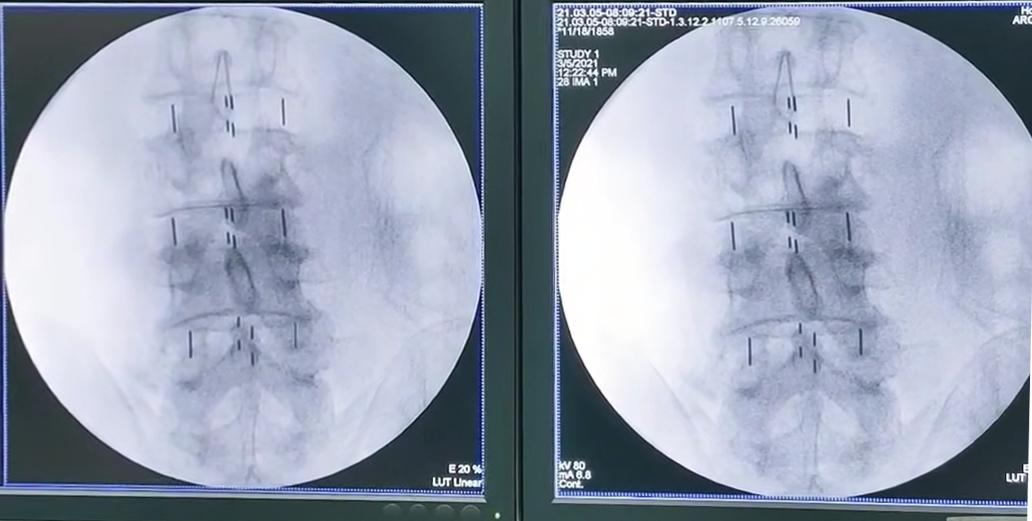

关于刘大爷的治疗,廖博主任解释:我们为患者成功实施了腰椎斜前方入路椎间融合术后路经皮内固定术。给这位病人采取了三个节段的手术方案,放完三个cage以后的,术中的X片,可以看到,患者的退行性的侧凸,已经得到了很好的修正,那么从2/3、3/4和4/5三个节段的cage,冠状位的一个矫形,效果非常理想。

从这张片子上看,我们就可以很明确的看到手术前后在影像学上的变化,还是非常明显的。术后,刘大爷腰腿疼痛的症状消失,走路姿势也恢复正常。